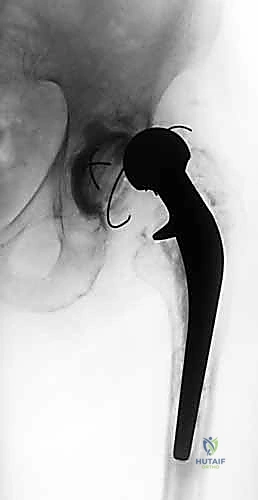

- الاستخراج المعقد (Implant Removal): يتم فتح المفصل بحذر شديد لحماية الأنسجة المتبقية. يقوم الدكتور هطيف باستخدام أدوات جراحية دقيقة ومتخصصة لإزالة المفصل الصناعي القديم (الساق المعدنية، الكوب الحُقي، والمسامير). التحدي هنا هو إزالة هذه الأجزاء دون التسبب في كسور إضافية للعظم الذي قد يكون هشاً بسبب العدوى.

- تشكيل ووضع المباعد الأسمنتي (Antibiotic-Loaded Cement Spacer): بعد التأكد من نظافة الحقل الجراحي، يقوم الجراح بخلط "أسمنت عظمي" طبي مع جرعات عالية جداً من المضادات الحيوية (يتم اختيارها بناءً على المزرعة البكتيرية السابقة).

- يتم تشكيل هذا الأسمنت ليأخذ شكل مفصل الورك المؤقت.

- وظيفة المباعد: يحافظ على طول الساق، يمنع انكماش العضلات المحيطة بالورك، والأهم من ذلك: يقوم بإفراز تركيزات عالية جداً من المضادات الحيوية مباشرة في مكان العدوى على مدار الساعة، وهو ما لا يمكن تحقيقه بالأدوية الفموية.

هناك نوعان من المباعدات:

* المباعد الثابت (Static Spacer): كتلة صلبة تمنع الحركة تماماً، يُستخدم في حالات فقدان العظم الشديد.

* المباعد المتحرك (Articulating Spacer): يشبه المفصل الحقيقي ويسمح ببعض الحركة، وهو المفضل لدى الدكتور هطيف متى ما سمحت حالة العظام بذلك، لأنه يسهل إعادة التأهيل لاحقاً.

- إزالة المباعد: يتم فتح الجرح القديم وإزالة المباعد الأسمنتي بحذر.

- زراعة مفصل المراجعة المعقد (Revision Arthroplasty): المفاصل المستخدمة في هذه المرحلة تختلف عن المفاصل الأولية؛ فهي مصممة لتكون أطول، وأكثر استقراراً، وتحتوي على آليات تثبيت معقدة لتعويض ضعف العضلات والأربطة. يتم تثبيت الكوب الحُقي الجديد وساق الفخذ بدقة ميكانيكية حيوية فائقة لضمان عدم تعرض المريض للخلع مستقبلاً.